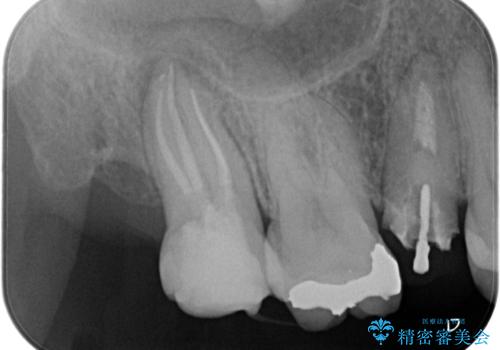

今回の精密根管治療では、まず治療中に唾液や細菌が入らないようラバーダムで患部を隔離しました。次に、肉眼では見えない根管内部を歯科用顕微鏡で拡大しながら確認。これにより、病変部を正確に特定し、感染源を徹底的に除去することができました。また、健康な歯質を極力残すため、必要以上に歯を削らないよう細心の注意を払って治療を進めました。治療後は、根尖部の病変がきれいになくなり、良好な経過をたどっています。これにより、大切な奥歯を残し、再感染のリスクを抑えることができました。